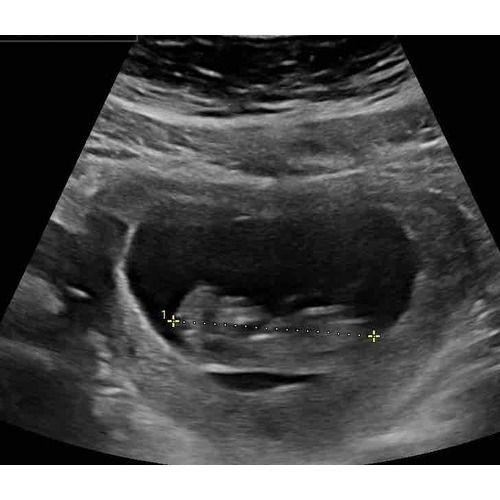

Nee, niks over gezegd. Zag er goed uit Incl hartslag. Echoscopiste die ook in het LUMC werkt.

Bij mij was mijn vruchtzakje ook helemaal niet mooi rond. De gynaecoloog heeft hier ook nooit iets van gezegd. Intussen is ze al bijna 5 maandjes oud🥰

Als ik naar al mij 4 keer de zwangerschappen en echo's heb gekeken rond de 6 weken was het bij mij ook allemaal hobbelig en niet mooi rond. 1 van alle is esn miskraam geworden maar dat konden ze niet zien aan de vorm ik heb het ook echt nog nooit gehoord... de volgende echo's werden ze al wat mooier rond... maar hun hebben ervoor gestudeerd... wanneer mag je terug?